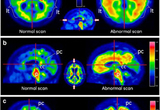

"알츠하이머 치매 시장의 개화"···듀켐바이오 치매 진단 방사성의약품 시장 의존도↑

- 2024-07-01 10:57

- 김민준 기자